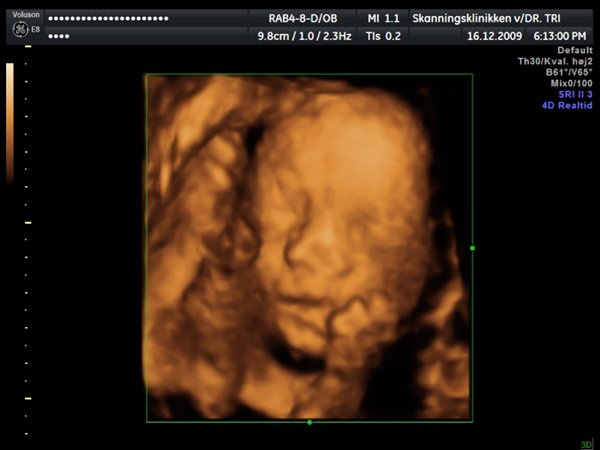

Ja, så var vi til 3D scanning med Ida igår. Og hvad kan jeg sige andet end hun er en meget træt pige

Jeg tror vi talte hun gabte mellem 10 og 11 gange under hele scanningen. Derudover havde hun meget travl med at gemme sig bag sine hænder som hun hele tiden åbnede og lukkede så det så ud som om hun vinkede

Billederne blev ikke så gode som jeg havde håbet, for lige som sin bror ligger hun meget tæt på moderkagen og med navlestregnen forand hovedet. Men de er ok, vi kan da se at hun ser sund og rask ud og at hun trives derinde.

Vedhæftede fotos (klik for at se i fuld størrelse)